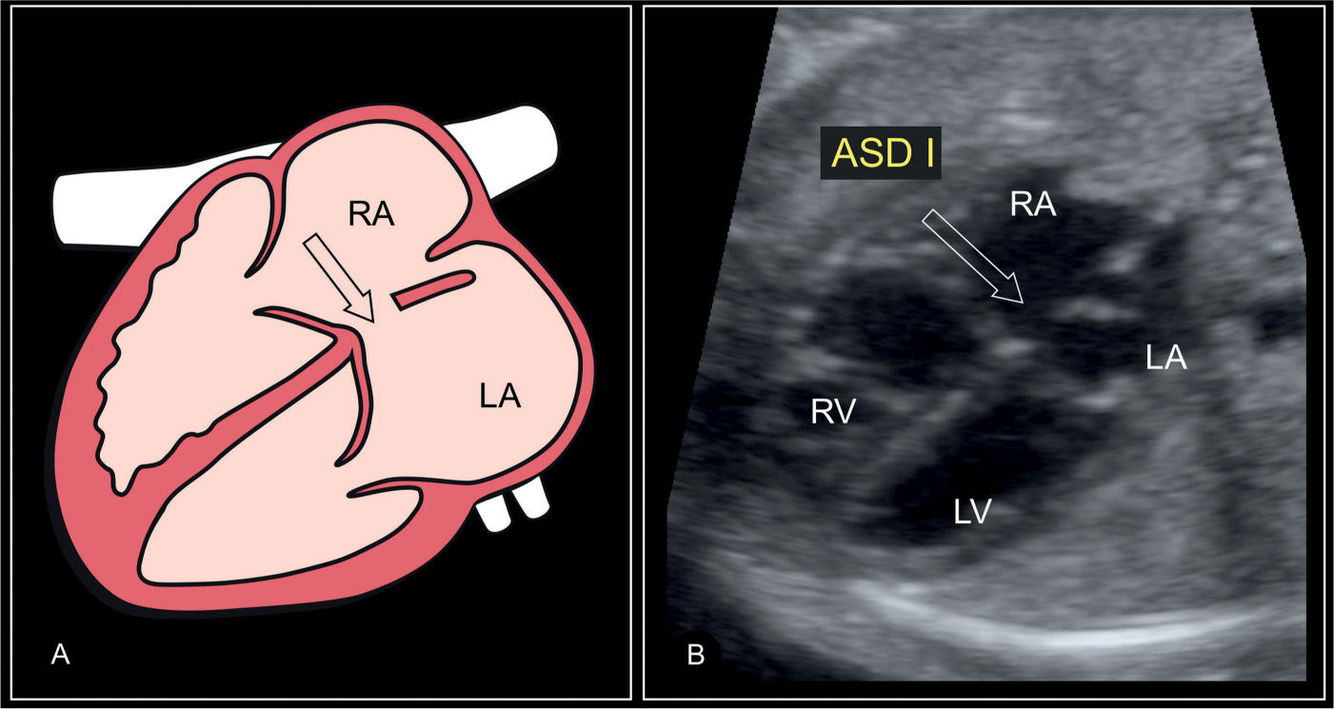

Artial Septal Defect